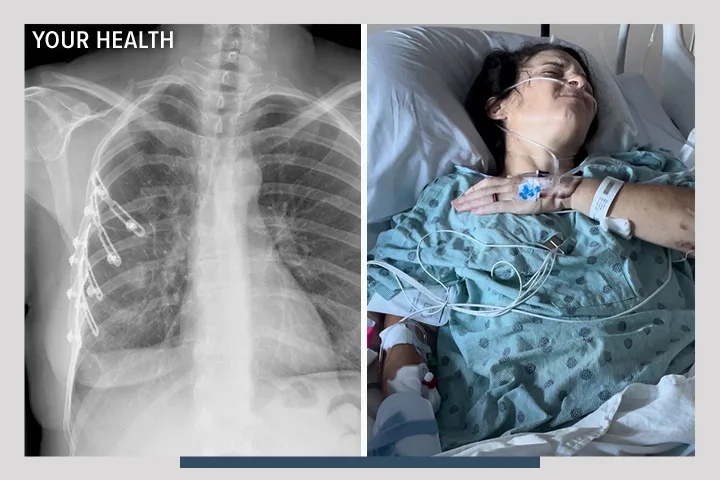

What if there was a better way to heal broken ribs?

Broken ribs cause agonizing pain and dangerous complications. Penn State created a better way to repair them with fewer risks and less pain.